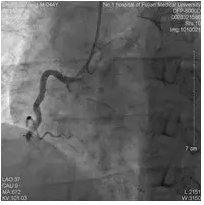

第二次手术过程

手术时间:2014年7月30日。

术中用药:术中追加肝素2000单位。

手术过程:送Elite导丝到LCX远端,沿Elite导丝送入MINI TREK 2.5×15 mm球囊到LCX病变处,以6-8 atm压力扩张后造影示狭窄减轻,TIMI血流3级。沿Elite导丝植入Firebird 2.75×33 mm支架到LCX病变处,TIMI血流3级。沿Runthrough导丝植入Firebird 4.0×18 mm支架到LM及LAD开口病变处, TIMI血流3级。

![]()